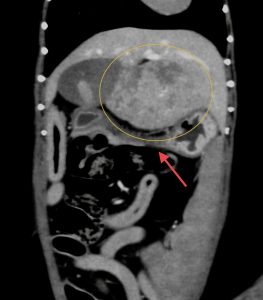

今回治療させていただいたワンちゃんは、数ヶ月前から肝臓(尾状葉乳頭突起)の腫れを指摘されており、CT検査で尾状葉乳頭突起に4センチ大の腫瘤性病変と胃の圧迫、重度の胆嚢拡張を認めました。肝臓腫瘍の初期はほとんど症状がなく(稀に低血糖)、腫瘍が大きくなることで他の臓器を圧迫して症状が出ることが多い印象です。

黄線:肝臓腫瘤

赤矢印:圧迫された胃